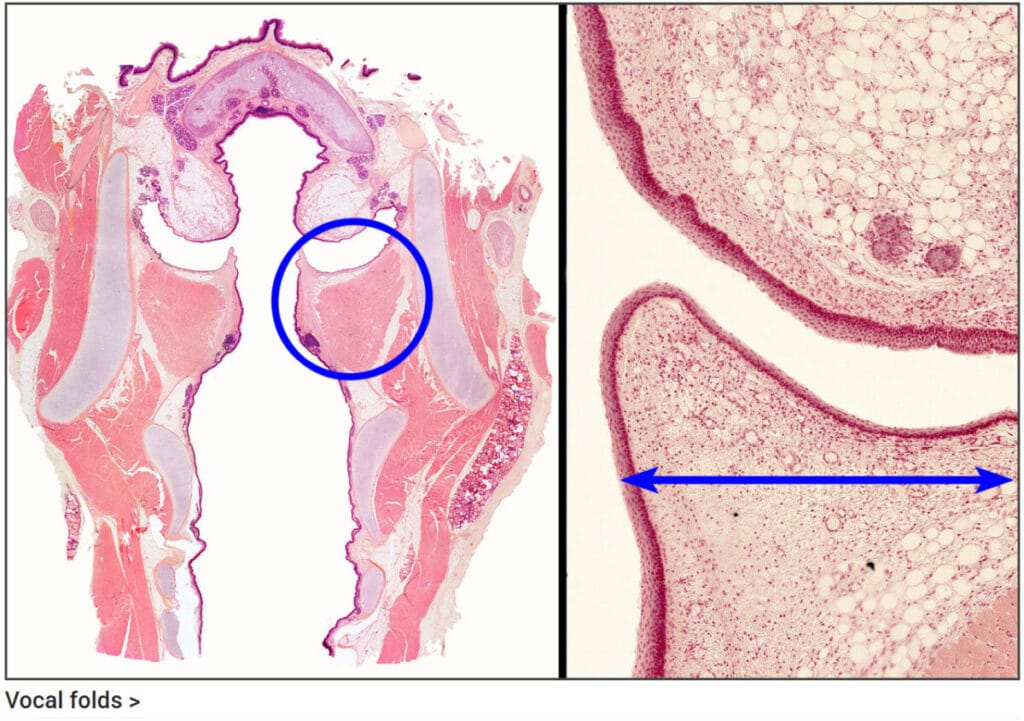

진성 성대주름 (True Vocal Fold)

발성을 담당하는 주된 구조물로, 진동을 통해 소리를 생성합니다.

| 상피 |

| ✅ 중층편평상피로 덮여 있습니다. |

| 내부 구조 |

| ✅ 성대근(vocalis muscle)과 성대 인대가 포함되어 있습니다. |

| ✅ 점막샘이 거의 존재하지 않습니다. |